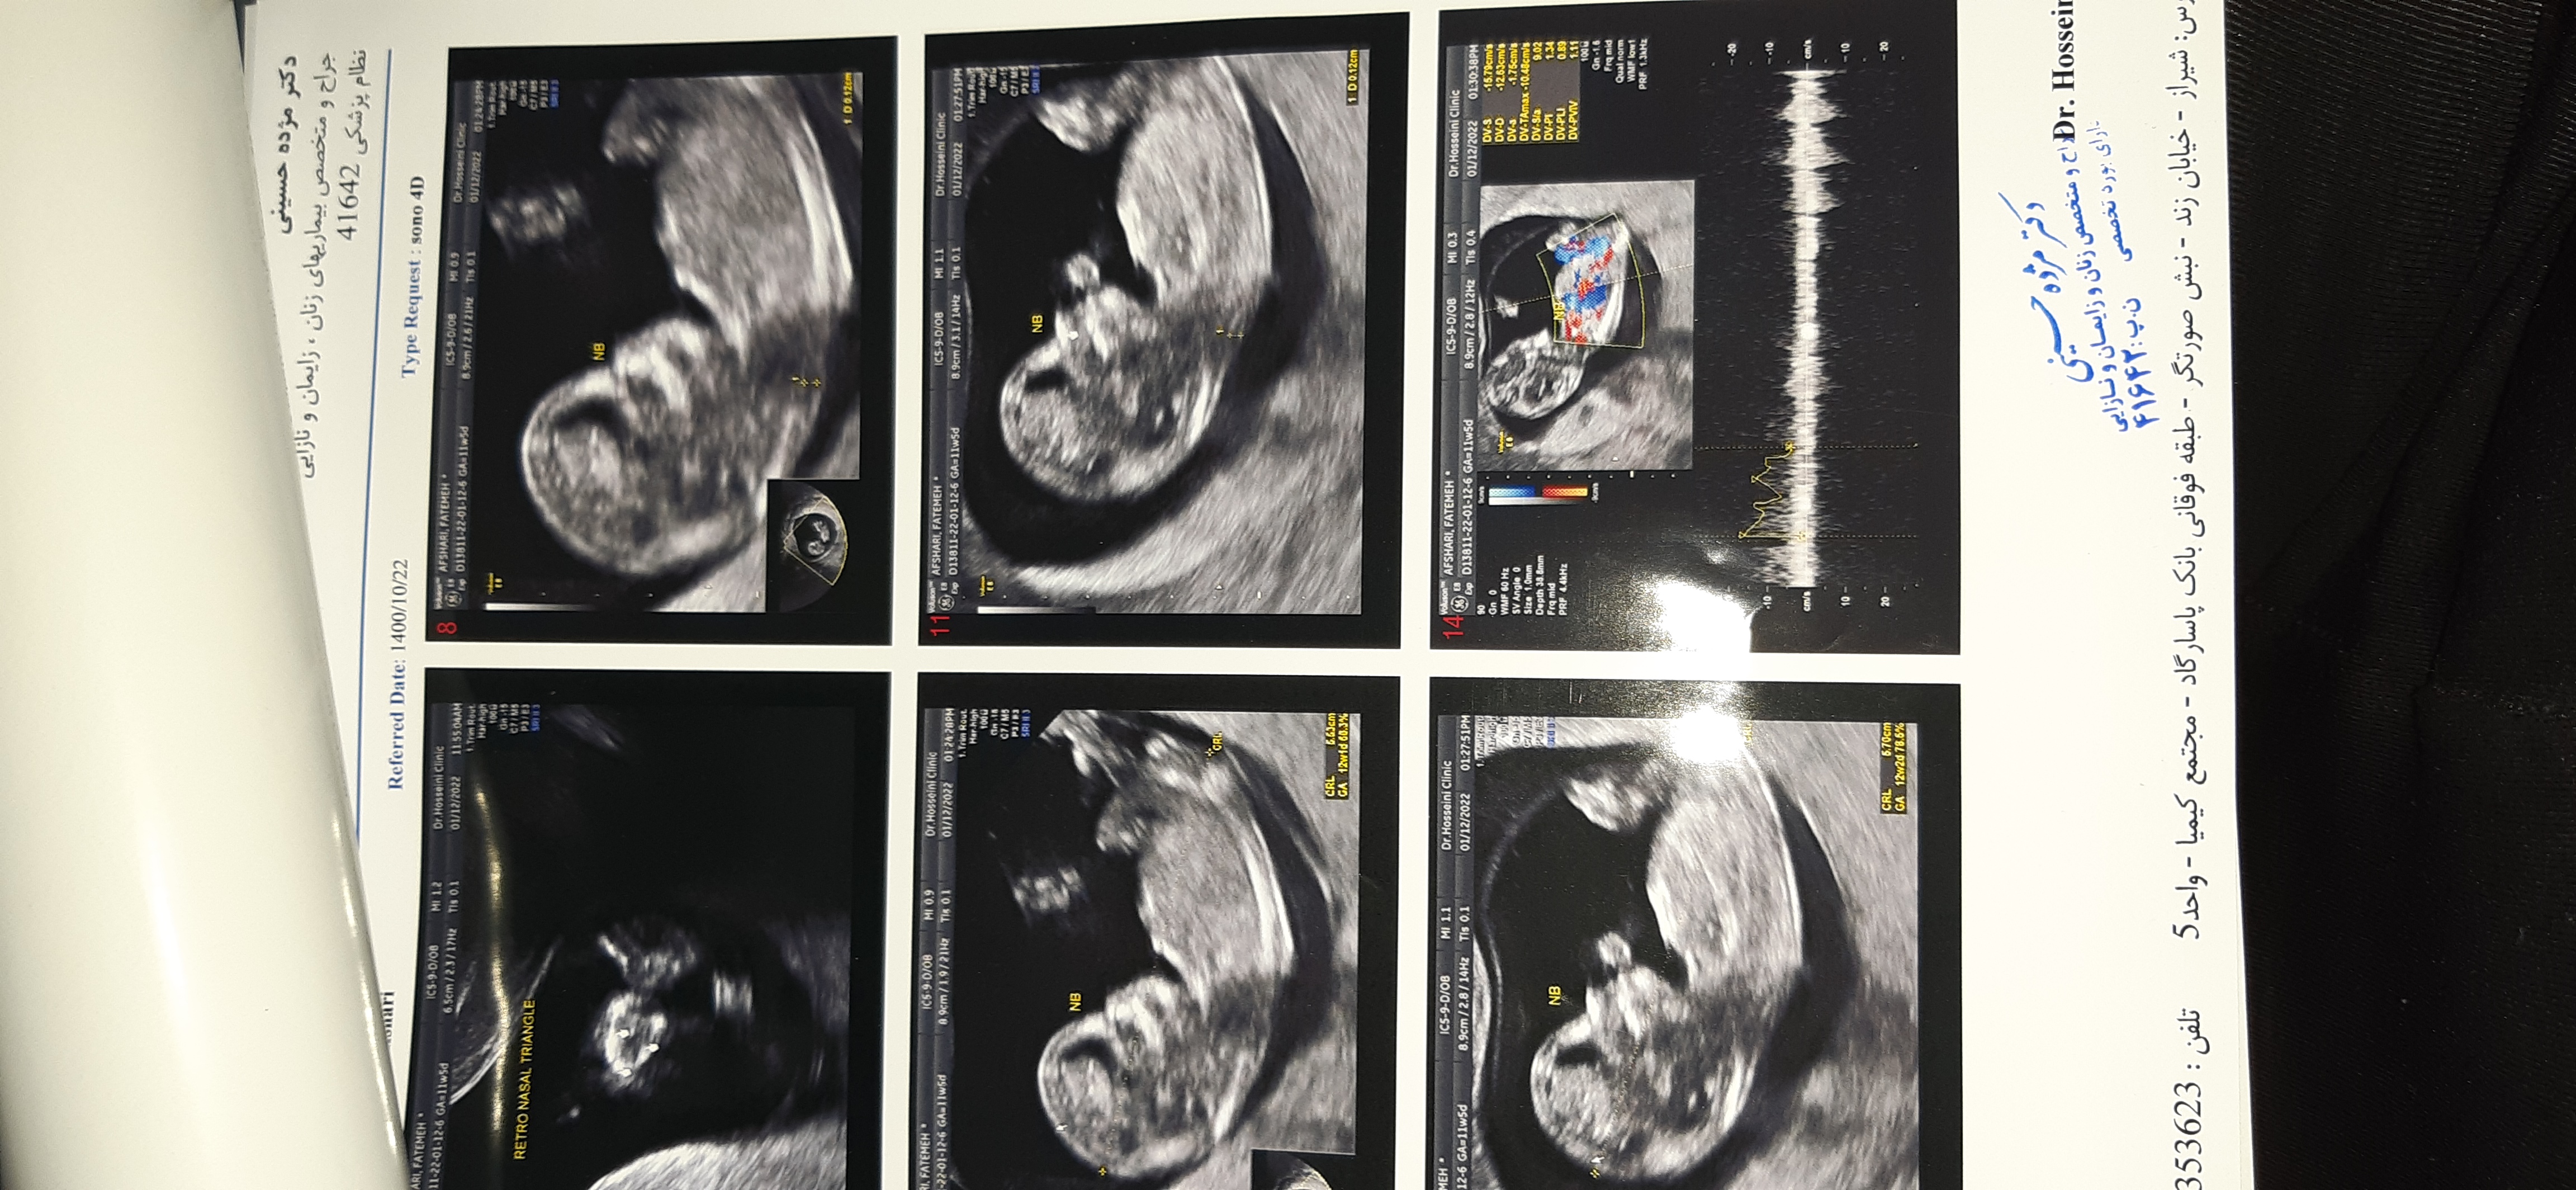

seeeeliiin عضویت: 1400/11/10 تعداد پست: 109 سلام عزیزم عکست خیلی ناواضحه ولی بخاطر تحدب پشتش حس میکنم پسره انشاالله صحیح و سالم باشه 💗😘 برای منم میشه بگی ????